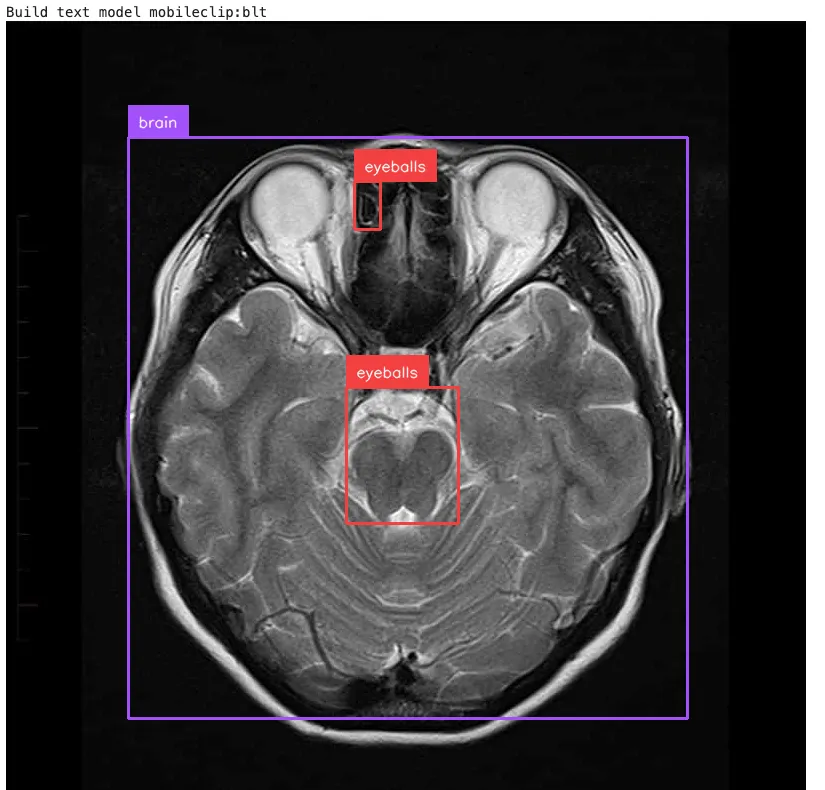

- 文本编码器:YOLO-E 首先使用 MobileCLIP-B(LT)文本编码器处理文本提示,以获得预训练的文本嵌入。

- 文字提示方式:

- 输入:图片+文字描述

- 系统使用 RepRTA 将对象嵌入与文本嵌入进行匹配

- 输出:与文本描述匹配的对象